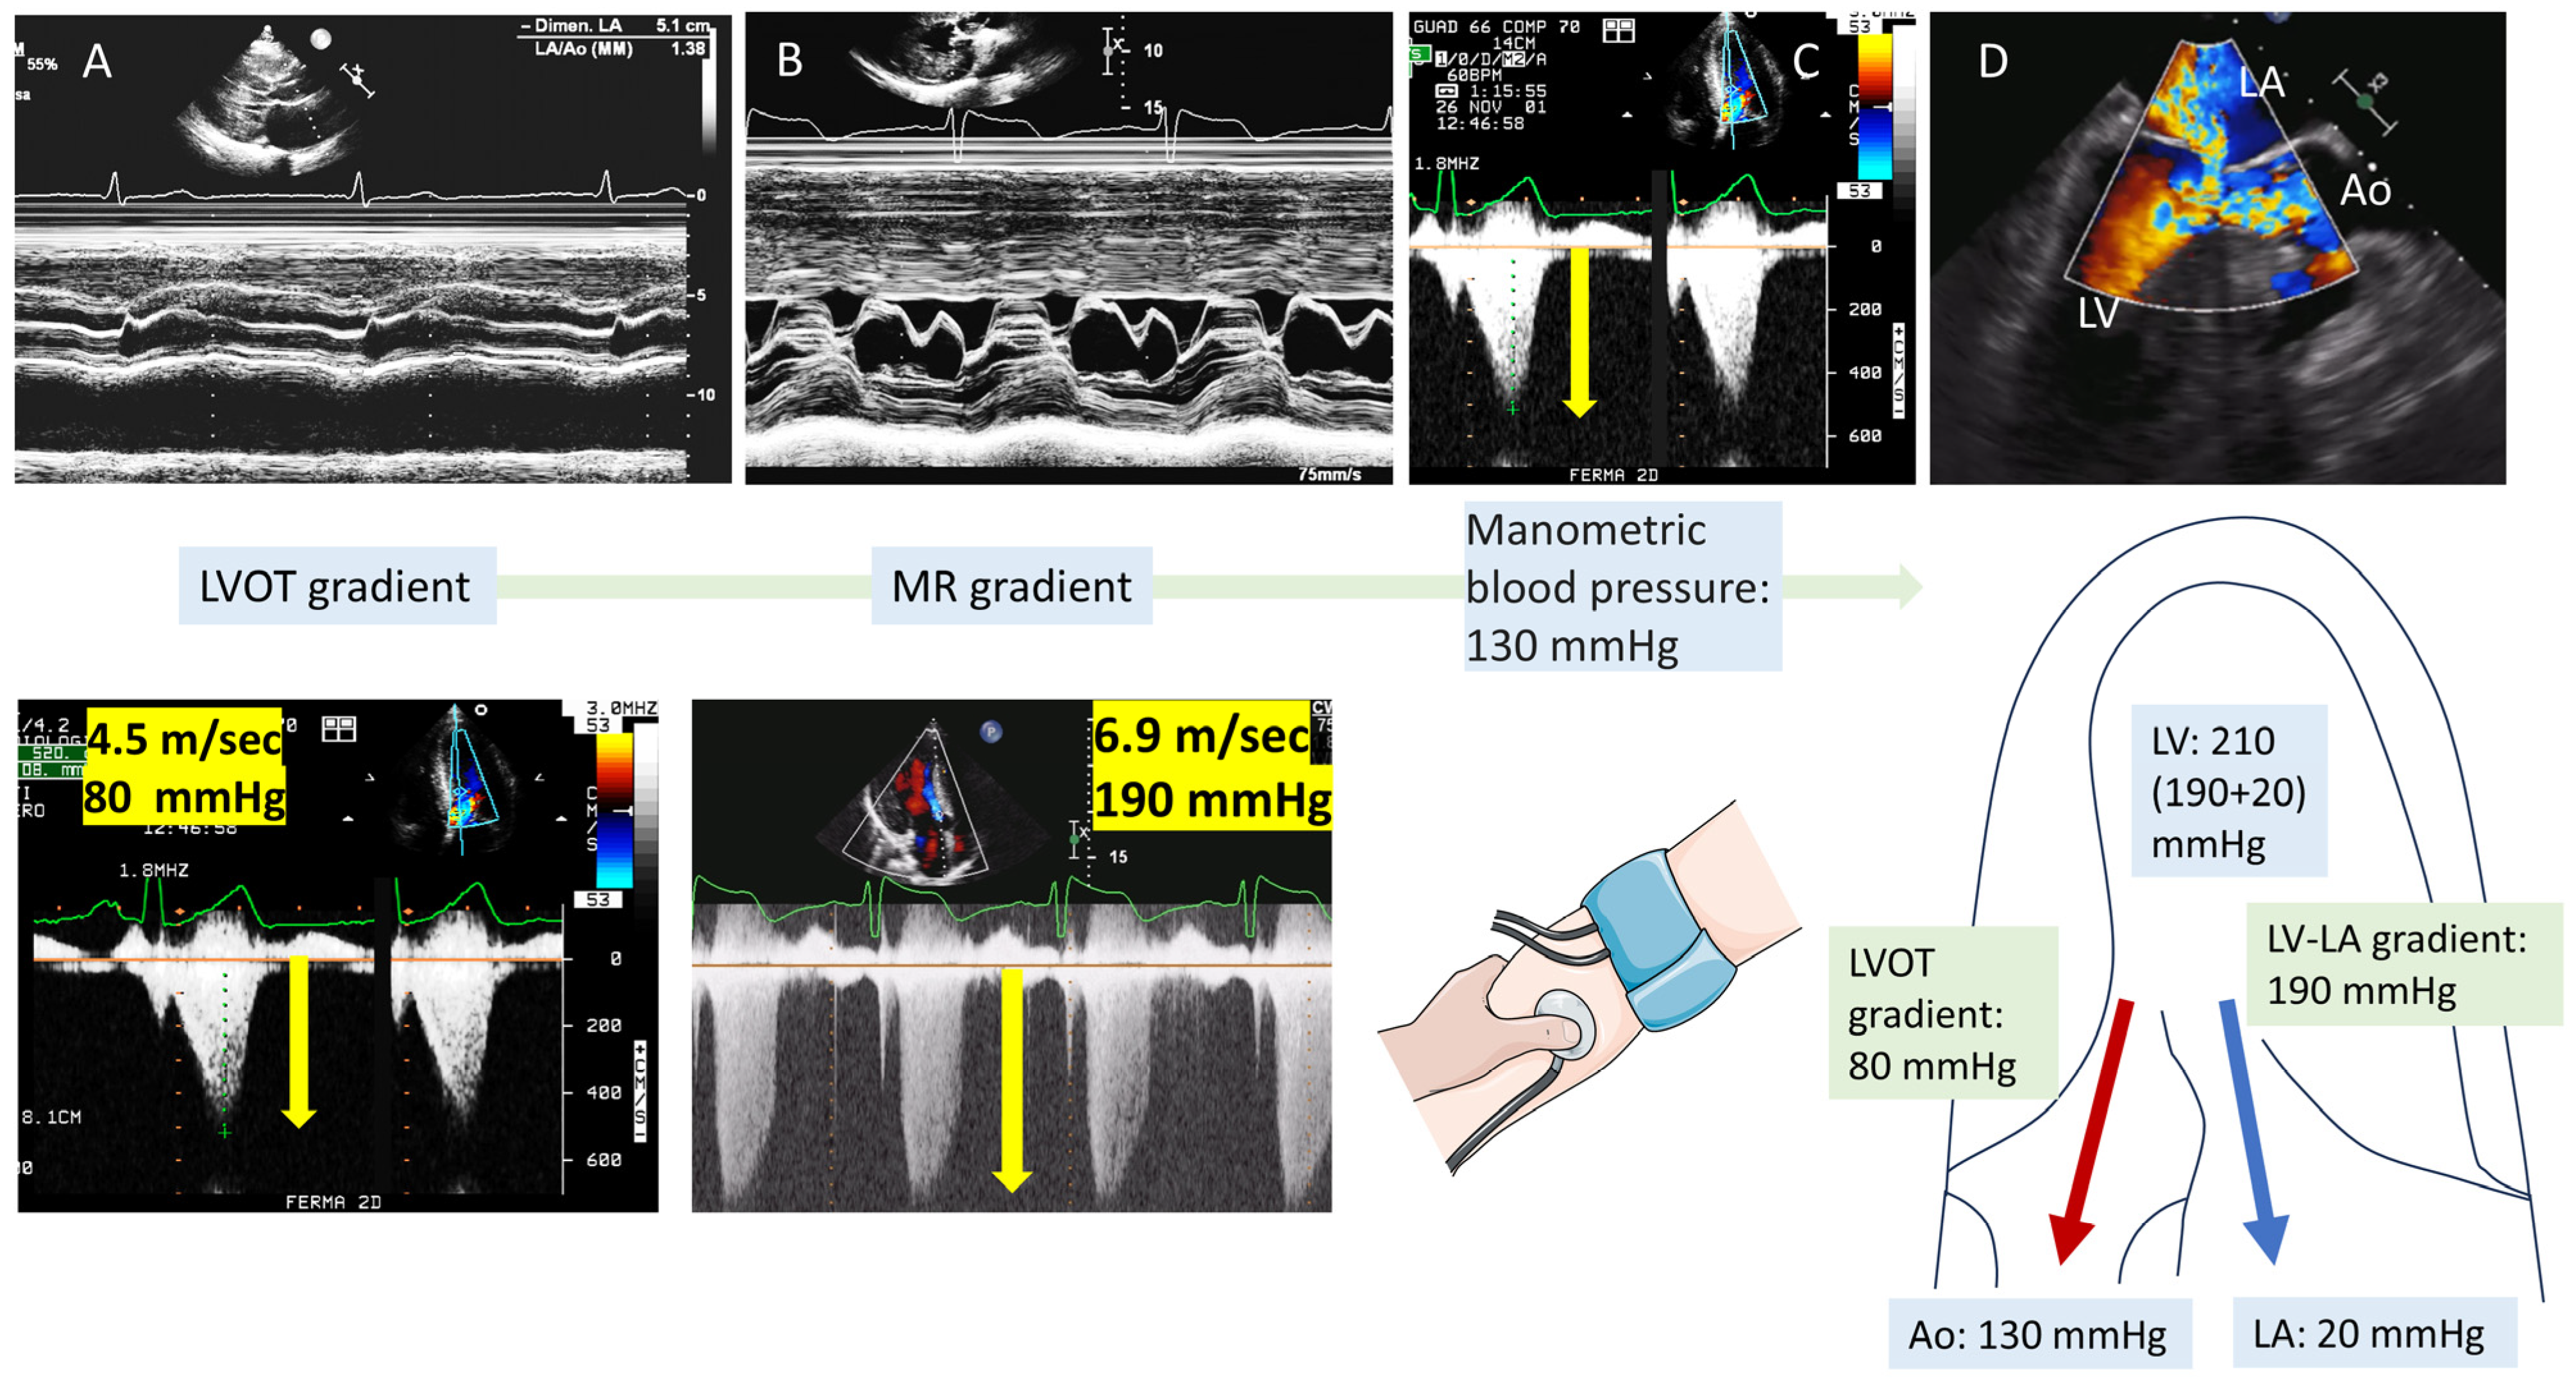

4. Tip and Tricks Concerning LVOT Obstruction Doppler Measurement

- Lo Russo, G.V.; Pepi, M.; Mushtaq, S.; Mantegazza, V.; Celeste, F. Is There a Typical Doppler Pattern in Patients With Apical Hypertrophic Cardiomyopathy With Aneurysm? JACC Case Rep. 2023, 14, 101836. [Google Scholar] [CrossRef]

- Abbasi, M.; Ong, K.C.; Newman, D.B.; Dearani, J.A.; Schaff, H.V.; Geske, J.B. Obstruction in Hypertrophic Cardiomyopathy: Many Faces. J. Am. Soc. Echocardiogr. 2024, 37, 613–625. [Google Scholar] [CrossRef]